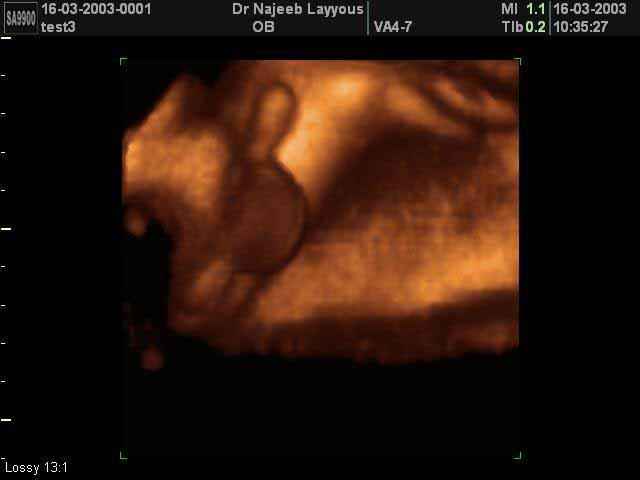

- Fetal Parts Ultrasound Scan Photos